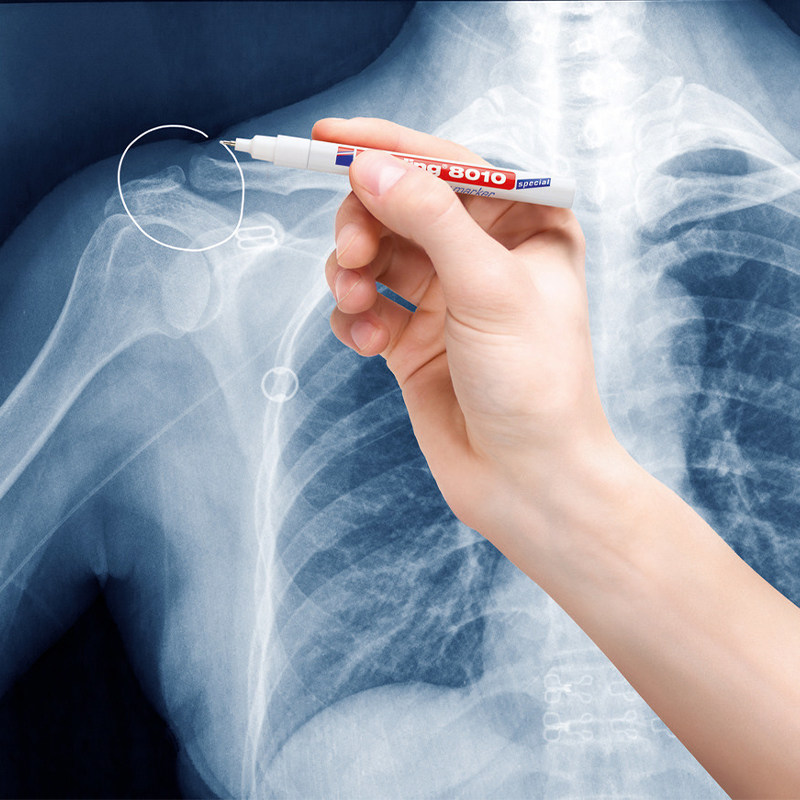

德国Edding 8010 X光片标记笔是一款非常实用的办公和学习工具。它的笔尖细腻,能够在X光片、相机胶卷和幻灯片上清晰书写,干燥迅速,不易晕染。无论是标记文档还是做简单的注释,均能轻松自如,不会影响图像的清晰度。此外,笔的油墨防水且耐光,非常适合长期储存的需要。整体使用体验非常满意,强烈推荐给需要进行标记的用户。

德国Edding 8010 X光片标记笔是一款非常实用的办公和学习工具。它的笔尖细腻,能够在X光片、相机胶卷和幻灯片上清晰书写,干燥迅速,不易晕染。无论是标记文档还是做简单的注释,均能轻松自如,不会影响图像的清晰度。此外,笔的油墨防水且耐光,非常适合长期储存的需要。整体使用体验非常满意,强烈推荐给需要进行标记的用户。